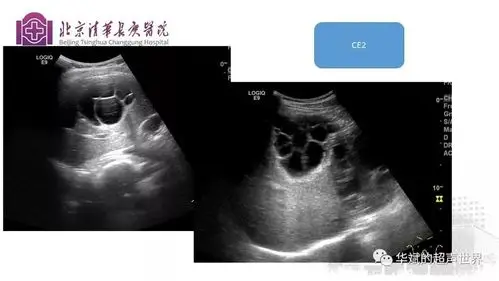

用针做手术--超声引导下穿刺抽吸联合微波消融治疗肝囊型包虫病

肝包虫病的超声声像图特征及其诊断价值

文献与病例学习肝包虫病的超声诊断